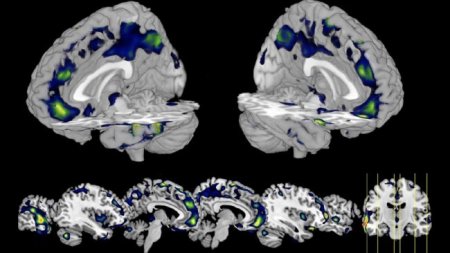

С помощью сканирования мозга можно диагностировать депрессию и болезнь Альцгеймера. Но можно ли объяснить поведение человека с помощью визуализации головного мозга? ?

, , . , , 2000 , . Nature.